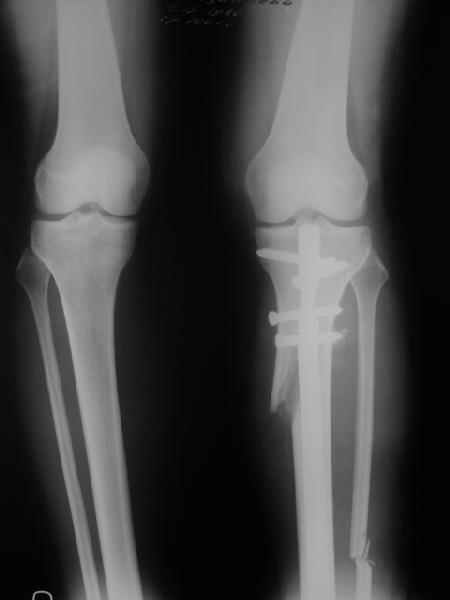

Отправитель: T. Derek V. Cooke 13 Сентябрь 2005, 23:51

|

Hello Alex:

Thanks for the clinical photo.

Your patient appears to have "Insquinting Knees"?

I am attaching a word doc with a 'print screen' of the program in use, showing the images being viewed and analysed

. On the right leg you can see some of the tools (from the tool bar above) applied to demonstrate a mild mech-axis varus of about 5 degrees.

On the left the bone landmarks used in the anlaysis are shown.

The data for the analysis are in the XLs sheet below, exported from the program automatically.

I have given a label of the abreviations and some normative values.

In essence she has a mild mech-axis varus of 7 degrees with some contribution from the femur (2) degrees and more from the tibia (6 degrees), none from the joint.

The analysis took about 6 mins.

Regards

Derek